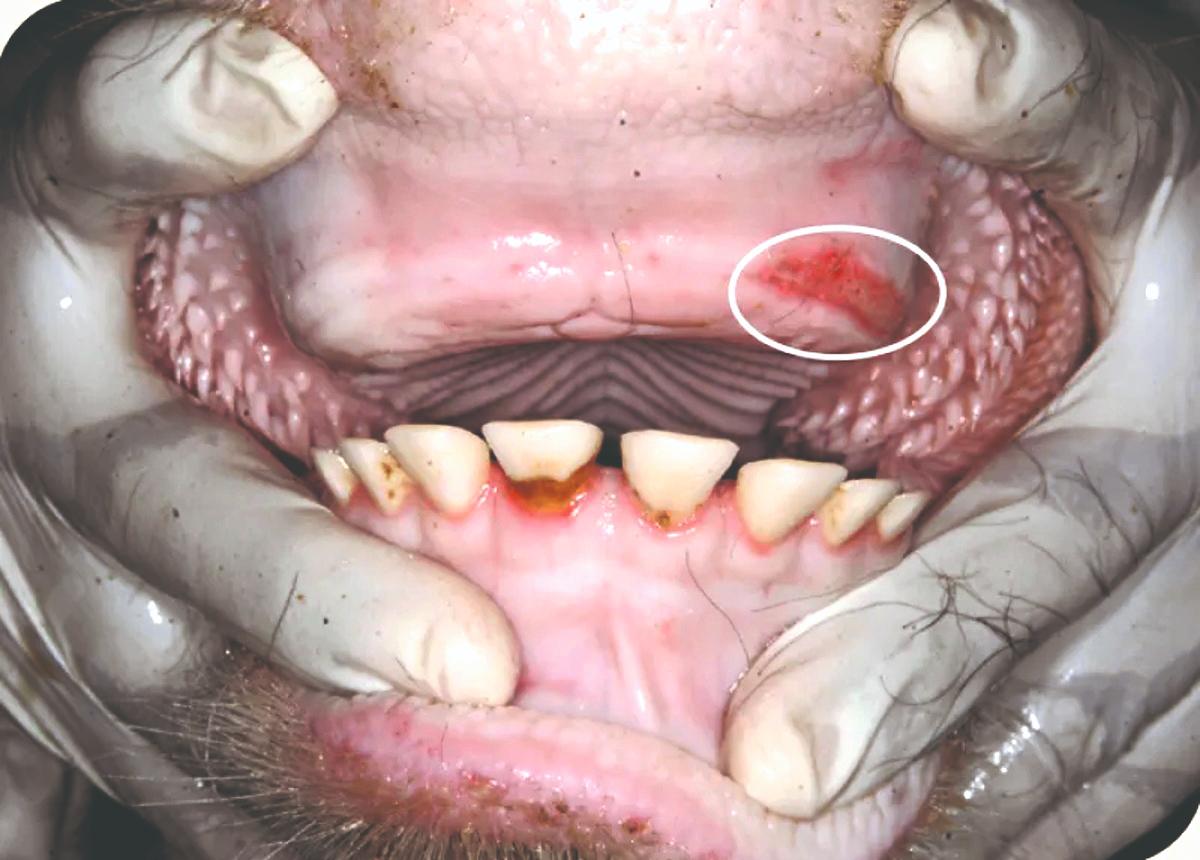

Prema trajanju stomatitis je pretežito akutna bolest. Ovisno o obliku stomatitis može biti kataralni, ulcerozni, nekrotični, vezikularni i granulomatozni. Najblaži oblik je kataralni stomatitis kod koje je sluznica blago otečena i crvena. Kod ulceroznog stomatitisa nastaju ranice i čirevi po usnoj šupljini, dok se kod vezikularnog pojavljuju mjehurići koji pucaju, nakon čega nastaju ranice. Odumiranje tkiva sa sivožutim naslaga po ustima popraćeno neugodnim zadahom iz usta karakteristično je za nekrotični stomatitis.Granulomatozni stomatitis karakteriziraju zadebljanja i kvržice (npr. kod drvenastog jezika) po usnoj šupljini.

Simptomi ovise o uzroku, brzini razvoja patološkog procesa, o stupnju bolesti te o trajanju. Zbog povećane osjetljivosti sluznice usta kod stomatitisa životinja otežano i polaganije žvače, odbija tvrđu hranu, prekomjerno slini, mljacka. U slini se mogu pronaći ostaci hrane i odljušteni dijelovi sluznice. Ovisno o vrsti upale primjetno je oticanje sluznice, prisutno je crvenilo, a ponekad su vidljive ranice, mjehurići (vezikule) ili naslage. Često je prisutan i neugodan zadah iz usta. Ako je uz stomatitis prisutan i opći infekcijski sindrom, odnosno povišena tjelesna temperatura, stomatitis smatramo znakom zarazne bolesti.